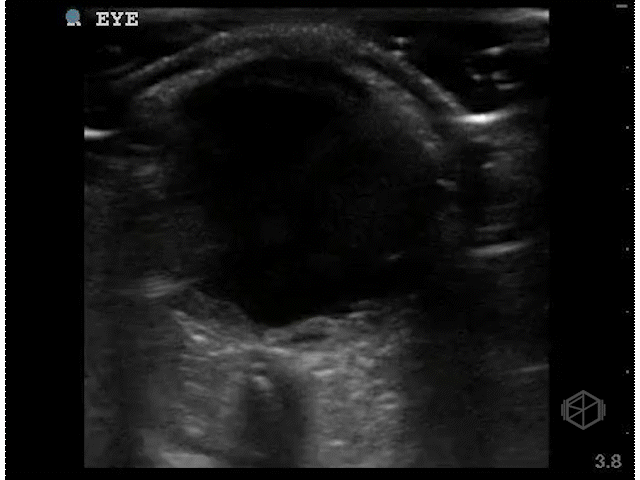

Dr. Singh scanned a ~40-year-old male with a past medical history of diabetes, hypertension, and substance abuse with diminished vision for 3 weeks.

Dr. Singh appropriately did the next step — he increased the gain significantly and performed oculo-kinetics (have the patient move their eye rapidly).

The above clips demonstrate some interesting pathology. There appears to be a hyperechoic flap tethered to the optic nerve. This patient has a retinal detachment. There may also potentially be a vitreous detachment.

• Retinal detachment appears as a thick hyperechoic membrane. It can be tethered to the optic nerve if large, or if smaller (or not close to to the optic nerve), attached to another portion of the posterior wall of the eye. The retinal detachment will move slightly with oculo-kinetics but will remained tethered. POCUS has a high sensitivity and specificity if done correctly for the detection of retinal detachments.